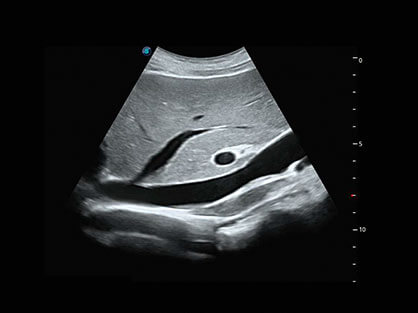

结合16877太阳集团超宽频带探头技术优势,能够更好地获得高分辨力与高穿透力的平衡,保证图像质量,为临床诊断保驾护航。

微米成像技术提升了对组织斑点噪声信号的抑制能力,并进一步强化边界信息,从而获得清晰图像。